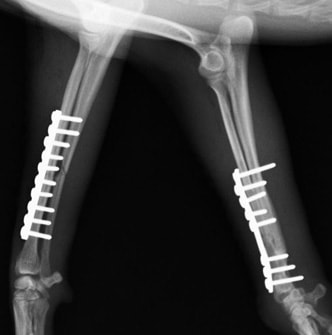

両前肢の骨折:橈骨尺骨骨折整復手術②

![]() 手術前レントゲン写真① |

![]() 手術後レントゲン写真① |

![]() 手術前レントゲン写真② |

![]() 手術後レントゲン写真② |